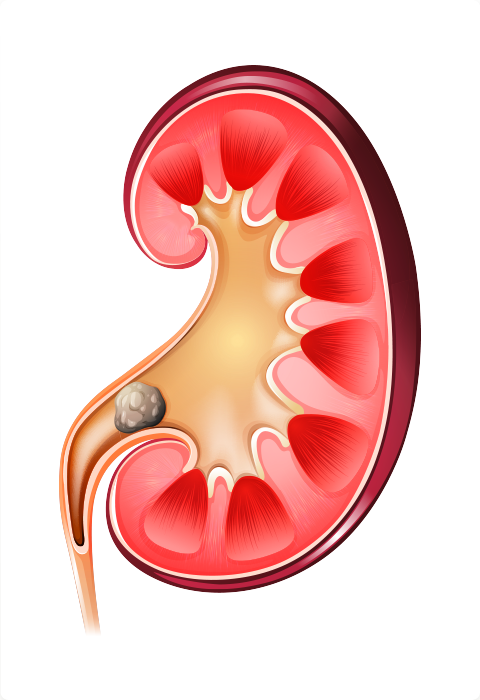

Litíase Urinária (Cálculo Renal):

A Litíase Urinária é uma doença global, com risco de ocorrer durante a vida de 12% nos homens e de 6% nas mulheres. A incidência de formação de cálculos começa aos 20 anos, atinge o pico entre 40 e 60 anos e depois declina. A obesidade aumenta em 30% a ocorrência de cálculos urinários em homens e dobra em mulheres. Cerca de 80% dos cálculos são constituídos por cálcio, seguidos pelos de infecção, com cerca de 10% e pelos de ácido rico, com cerca de 7%. Grande parte dos cálculos é de origem mista, portanto, difícil de identificar um fator causal.